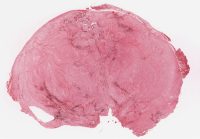

CANP2008-5.svs

12000 x 17372

@ 20X